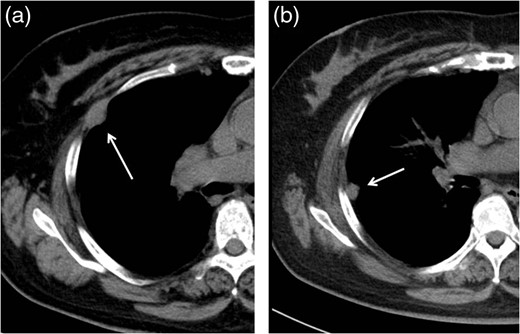

A 60-year-old woman was referred to our hospital with an anterior mediastinal tumor on computed tomography (CT) performed for follow-up 6 years after a complete response to chemotherapy for malignant lymphoma. CT revealed a tumor in the right anterior mediastinum with a diameter of 3.5 cm, round shape and demarcation from the neighboring tissue (Fig. 1). No recurrent lesion of the malignant lymphoma was detected. She had no symptoms, including none due to myasthenia gravis. Her anti-acetylcholine receptor antibody level was 0.2 nmol/L (within normal range). To confirm the diagnosis and treat the patient, we planned tumor resection via VATS.

Initial CT revealed a tumor in the right anterior mediastinum with a diameter of 3.5 cm, round shape, which was clearly demarcated from the neighboring tissue.